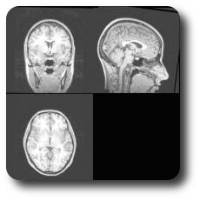

During neuronavigation, the head of the subject is displayed in different modes:

-

3D reconstruction of the scalp (either in standard colours or using the grey tones coming from MRS)

3D reconstruction of the brain (either in standard colours or using the grey tones coming from MRS)

Axial view of magnetic resonance images

Next to each of these display modes, the coronal and sagittal views of MR images are displayed, which are constantly updated and lined up during neuronavigation to show the effective point reached by stimulation.

| MR Images of the subject | Reconstructed MR Images |